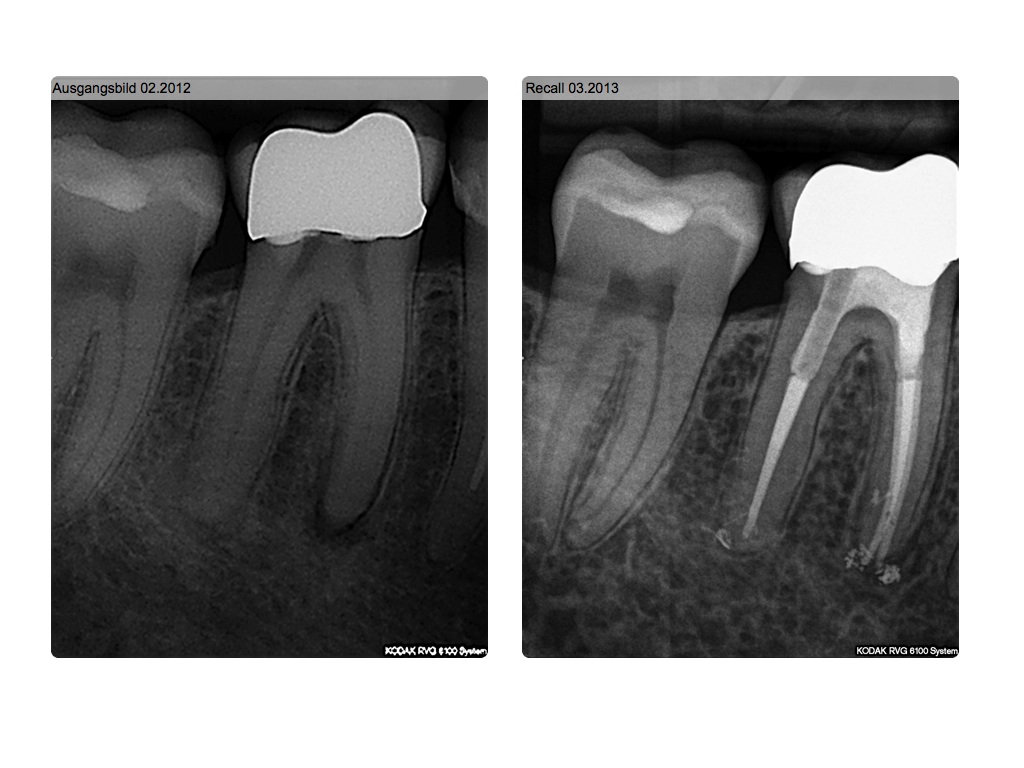

P. apicalis im Recall